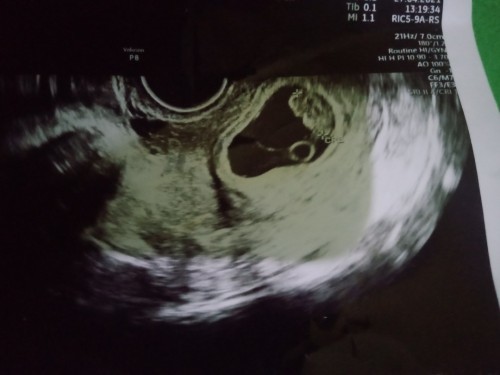

Bun Kehamilan sya 7 mnggu udh ada bakal janinnya tpi TDK ada detak jantungnya, blm terdeteksi..

Solusinya dong Bun, msih kepikiran ajh nih

hallo bunda selamat atas kehamilannya🤗janin mulai d kasih ruh itu di usia 4 bulan ya bund,jdi wajar klo usia segtu tidak terdeteksi,7w baru penebalan rahim ya bund jdi tidak usah khawatir😉 saya hamil anak k 3 usia 16w kmren habis priksa detak jantungnya sudah terdengar tpi masih sangat halus, semoga sehat sellau ibu dan janinnya ya🤗

Baca lagibiasanya pasti disuruu dtng lgi 1-2minggu.. krna kalo teori 7 udh ada detak jantung .. tpi ada juga yang di 8 smpe 9 minggu bru ada. mudah2an detunya sehat yah krna di liat dri usg bagus udh ada bakal janin nya ..

Gapapa bun, saya juga usia 7 minggu belum ada detak jantungnya dan disuruh cek 2 minggu lagi dan ternyata sudah ada😘

q kmren USG 10w br ada detak jantung .. mngkn 7w msh belum ya... q usg 6w5d cuma kantong aja... hehe, jd jgn panik bun